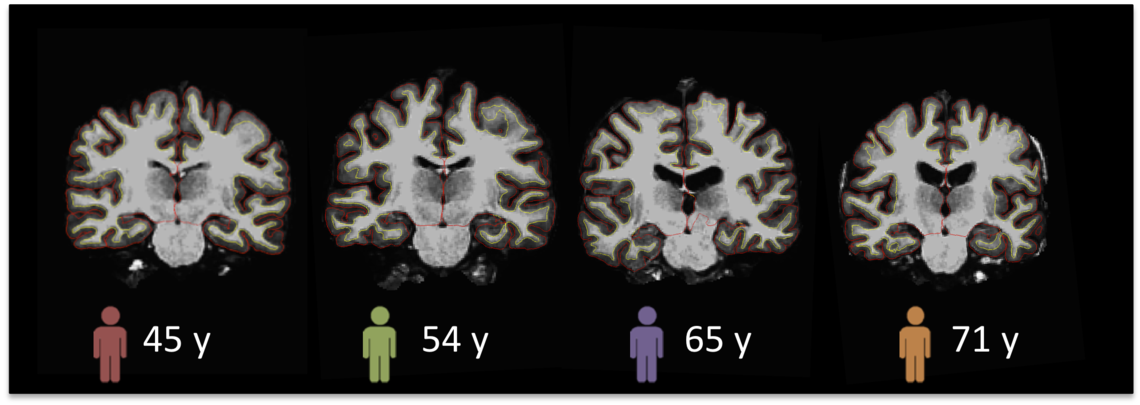

The Calgary Normative Study (CNS) is an ongoing, longitudinal study of normal human brain aging which focuses on acquiring quantitative MR imaging structural and functional data. The CNS began in 2014 and to date over 475 subjects have been enrolled (18-90+ years) with over 250 subjects having had follow-up imaging after a period of approximately 3.5 and 7.0 years. We anticipate enrolling additional subjects and acquiring follow up data at 10.5 years and later.

Each subject receives an imaging battery (including T1 morphology, perfusion and diffusion imaging, resting state fMRI, quantitative susceptibility mapping), resting-state fMRI and T1 and T2 relaxometry, plus a simple cognitive test, short neuropsychological assessment, and acquisition of a medical history. See our "protocol" paper: